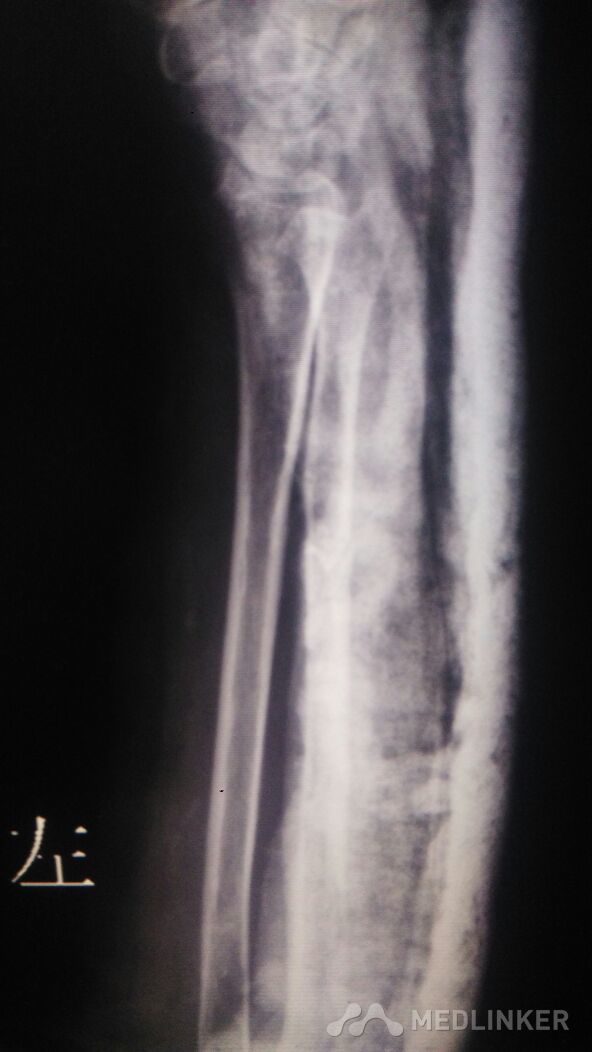

左侧尺骨骨折的治疗。

骨折 尺骨骨折

左前臂外伤后,尺骨肿痛,稍畸形。可触及骨擦感。左前臂活动受限。

骑电动车摔倒致左前臂肿痛3小时,左前臂以尺骨处压痛阳性,叩痛阳性。

左前臂尺骨骨折,给行保守治疗。